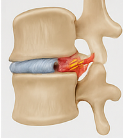

척추관 협착증

허리 속 신경이 지나는 통로가 좁아지는 상태가 척추관 협착증입니다. 허리통증 원인 중 이 질환은 특히 보행 시 통증이 심해지는 특징이 있어요. 오래 걷다 보면 다리가 무겁고 통증이 와서 멈췄다 다시 걷는 증상이 나타납니다.